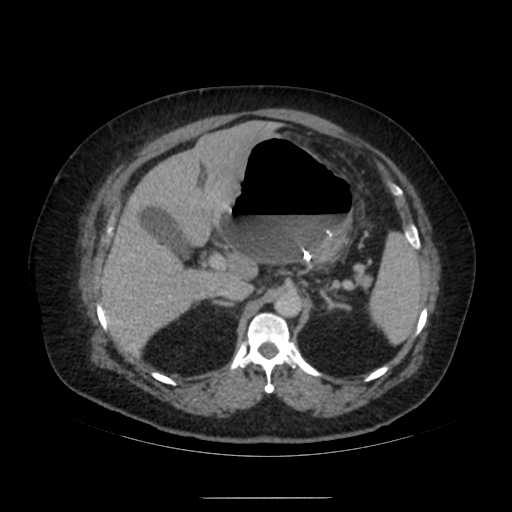

수술 후 복강 내 상태를 확인하기 위해 복부 CT를 촬영함.

복부 CT를 보면 수술부위 쪽으로 아주 큰 pocket이 형성되고 그 안쪽에 air-fluid level이 형성되어 있는 것을 확인할 수 있음.

해당 부분은 수술로 문합을 한 GE junction 쪽으로 염증의 위치로 생각할 수 있음.

추후 외과 과장님께 들어보니 sleeve op. 이후 leakage가 주로 생기는 위치는 gastro-esophageal junction 쪽이며, 천장으로는 liver(간), 좌측으론 spleen과 omentum이 있어 주변으로 염증이 퍼지지 않고 위 사진처럼 갇힌 형태의 염증이 생성된다고 한다.

1. About 14cm sized air-containing complicated fluid collection around the stomach.

: probable leakage at sleeve gastrectomy site.